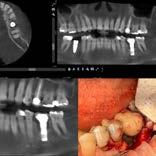

Cirujano dentista con especialidad en periodoncia e implantes dentales. Posee un fellowship oral. Miembro del Colegio de Cirujanos Dentistas de Puerto Rico y del American Association of Periodontology. Presidente de la Asociación de Periodoncistas de Puerto Rico.

La doctora Frances M. Herrero se graduó Magna Cum Laude de Bachillerato en Ciencias del Colegio de Mayagüez y Suma Cum Laude del Recinto de Ciencias Médicas, Escuela de Medicina Dental. Especialidad en Periodoncia de la Universidad de Maryland. Pertenece al Colegio de Cirujanos Dentistas; Sociedad de Especialistas en Periodoncia e Implantología de Puerto Rico, Sociedad Americana de Periodoncia y es Board eligible en Periodoncia.

Comenzó su trayectoria académica en la UPR de Mayagilez, donde obtuvo su Bachillerato en Biología. Luego continuó sus estudios en la Escuela de Medicina Dental de la Universidad de Puerto Rico de Ciencias Medicas, graduándose con su título de Doctor en Medicina Dental (DMD) en 2013. El Dr. Reinaldo Deliz Guzman está profundamente comprometido con la excelencia en la atención periodontal y se enorgullece de servir, a la comunidad local en PR,

Infección en Implantes